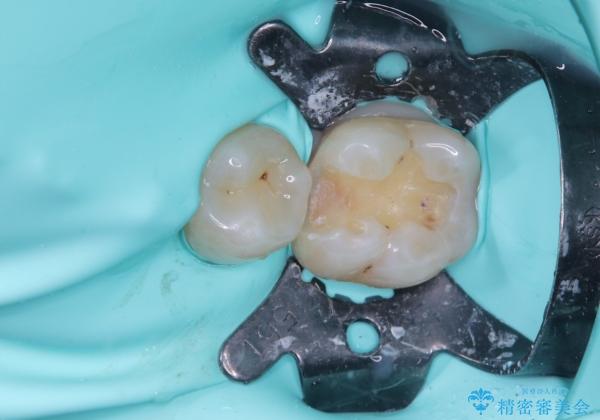

精度の良いインレーを製作するために、シリコーンにて型どりしました。

また確実な接着操作を行うために、インレーを接着する際にはラバーダム防湿を行いました。